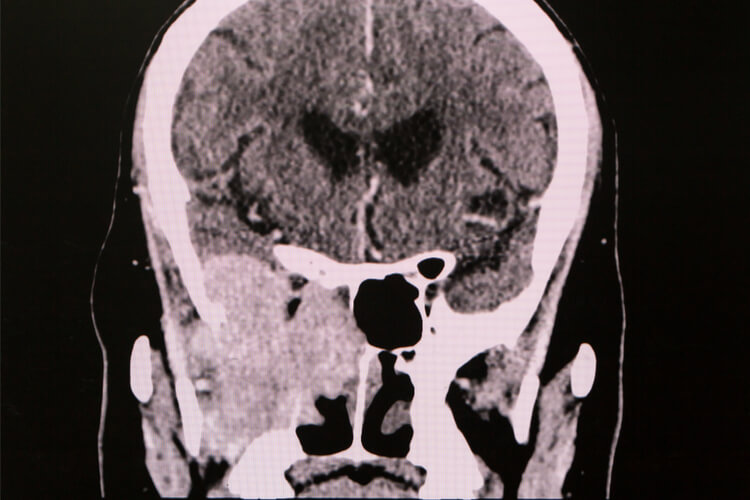

Initially, a biopsy performed in the office is required to confirm the type of tumor (benign versus malignant) and its grade (degree of mutation). Imaging (in the form of CT and MRI) is required to determine the spread. After this, the treatment plan will be developed. Malignant tumors in the sinonasal cavities, outside of lymphoma, will always require surgical removal and possibly require radiation +/- chemotherapy. However, these details will largely depend on the findings described above.

sinus-cancer-scan